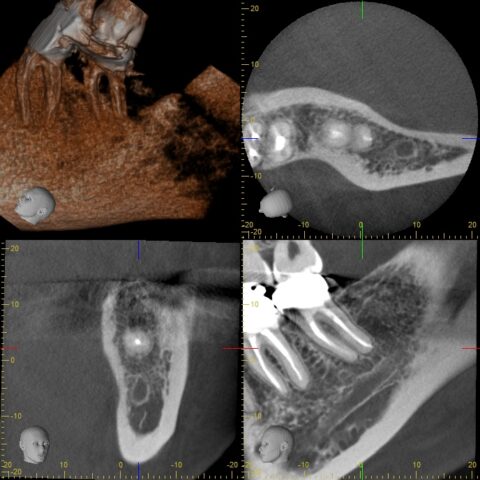

before

after

| 症状 | 検査をしてほしい |

|---|---|

| 年齢・性別 | 30代 女性 |

| 治療期間・回数 | 治療回数 約1ヶ月 |

| 治療方法 | 精密根管治療+PGA Cr |

| 費用 | 約20万 |

| 治療前の注意点 | ラバーダム防湿は必須 |